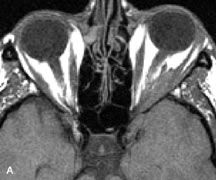

Inflammatory and Lymphoproliferative Lesions

Inflammatory conditions of the orbit, both idiopathic (inflammatory pseudotumor) and those of known causes, have been found to be hypointense to fat and isointense to muscle on Tl-weighted studies and isointense or slightly hyperintense to fat on T2-weighted images (Fig. 21).50,64,69 The more fibrous or sclerosing varieties have less signal intensity on T2-weighted images. Marked enhancement is seen in pseudotumor infiltrates after gadolinium administration.70 The same signal characteristics are demonstrated in patients with Tolosa-Hunt syndrome, with mass lesions seen in the cavernous sinuses and orbital apices.71

Fig. 21. A. T1-weighted MR scan demonstrates diffuse enlargement of both the superior rectus and levator palpebrae superioris muscles (single arrows). The involvement of the tendinous insertions and preseptal soft tissues (open arrows) as well as lack of involvement of other muscles helps differentiate this entity from thyroid-associated orbitopathy. B and C. Postcontrast fat-suppressed T1-weighted MR scans demonstrate extensive enhancement of the involved muscles as well as the preseptal (open arrows) and perinuscular tissues (double arrows).